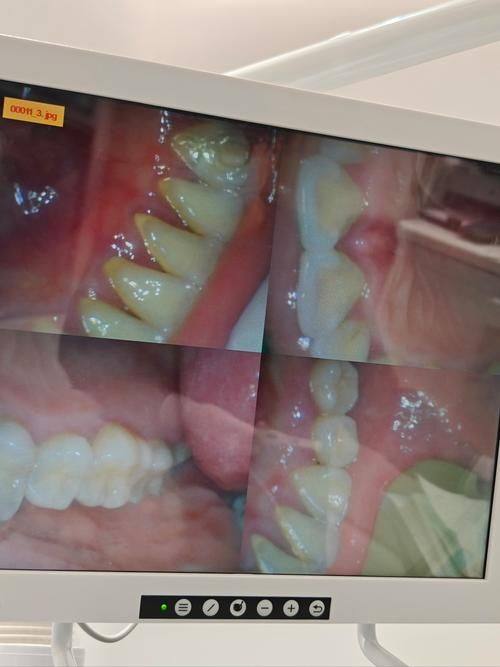

广东云浮同泽口腔门诊部一直以优质服务为目标,让口腔健康触手可及。它是正规的口腔诊疗机构,为牙友们提供全方面的口腔服务。诊疗项目丰富,涵盖补牙、洗牙、根管治疗、种植牙、牙齿矫正等。在技术方面,始终坚持为患者提供高端的口腔技术,并且融合了医术不错的口腔医生,还为大家定制专属设计,手术中追求细节,把控降低风险。诊疗环境舒适宜人,能缓解患者的紧张情绪。医院配备精良的设备,为诊疗提供有力支持。经过多年发展,不仅有名度提高,成功实例也不计其数,在当地患者中拥有良好的口碑。

1. 种植牙技术:拥有专精的医生团队,能够根据患者的口腔情况和需求,选择合适的种植体,为患者提供稳定、持久的种植牙解决方案。